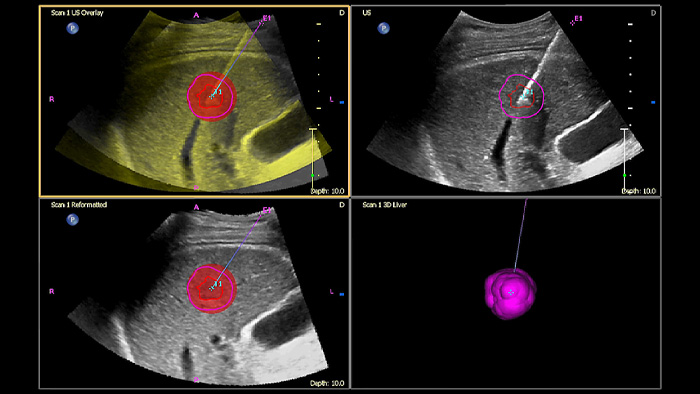

Planifiez et ciblez les lésions avec Tumor contour, un outil semi-automatique pour tracer un contour 3D autour d'une structure d'intérêt. Résultat : un guidage amélioré de la procédure dans les cas difficiles où la lésion n'est pas facilement visualisable.